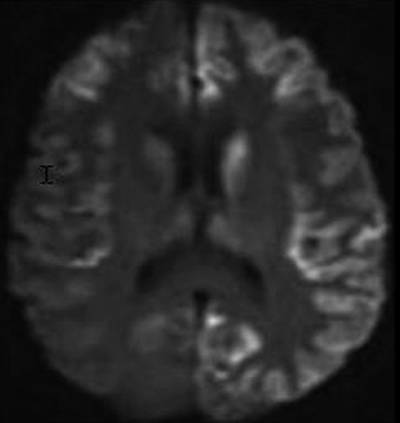

病例2:男,70岁。DWI轴位:双侧尾状核、丘脑及大脑皮层呈高信号。

变异性CJD